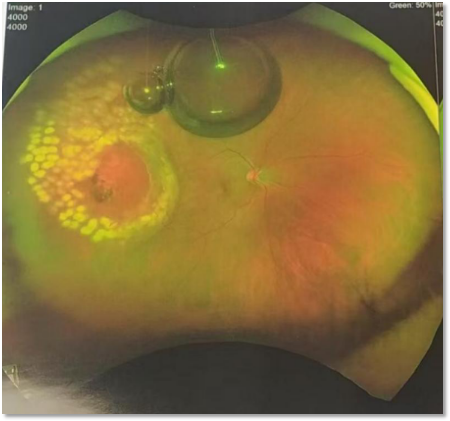

【手术前,赤道后大裂孔导致视网膜脱离】

传统方案常采用内路手术(玻璃体切除术),通过切除患眼玻璃体、复位视网膜、眼内激光封闭裂孔、气体或硅油填充玻璃体腔。不仅创伤大、操作复杂,术后需长期保持特殊体位,且费用高、恢复慢,并发症风险较高。外路(巩膜扣带术)损伤小,但后部大裂孔手术操作困难。

不久前,患者王女士(化名)因视物模糊、视野遮挡就诊,经韩清院长团队初诊,确诊为孔源性视网膜脱离,裂孔大,且位于眼球赤道后。「裂孔越大,视网膜脱离进展会越快,诊疗窗口期更短。」韩清院长回忆道。